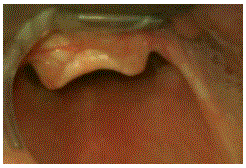

Durante a laringoscopia direta realizada com posicionamento ótimo por operador experiente, observou-se a seguinte visualização glótica.

Dentre as alternativas abaixo, a conduta mais adequada neste momento é a intubação com: